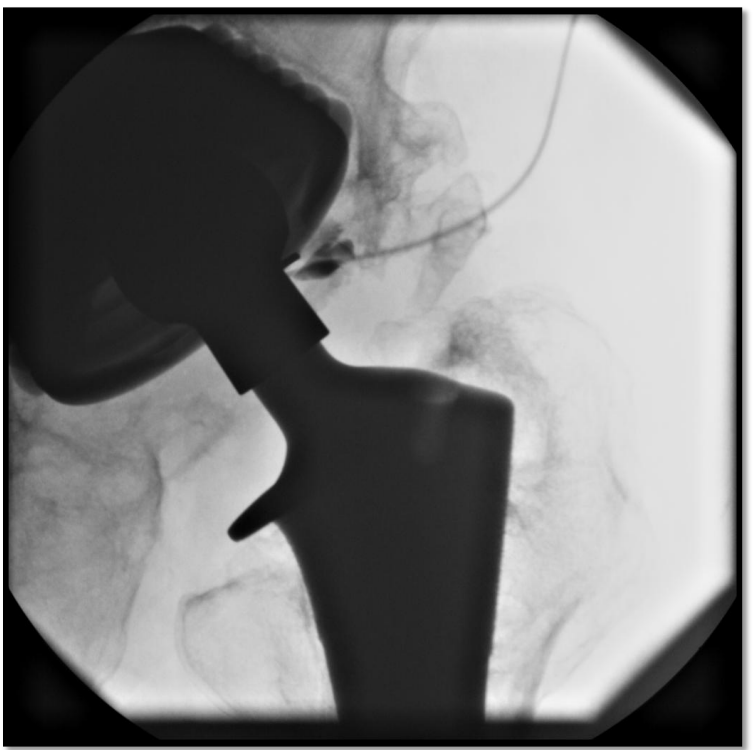

What is a joint aspiration

A

• similar to needle aspiration biopsy

• used on patients who have a joint replacement

• sample sent out to the lab to rule out infection

• patient would have PICC line

need to redo to confirm infection is gone

Q

What is a Joint injection

therapeutic to try and reduce pain in joint. (steroid, hyaluronic acid joint injections – Synvisc, Orthovisc, Neovisc, etc )

- pain releif (oil change in joint)

dont need fluoro with knee but need it with hip